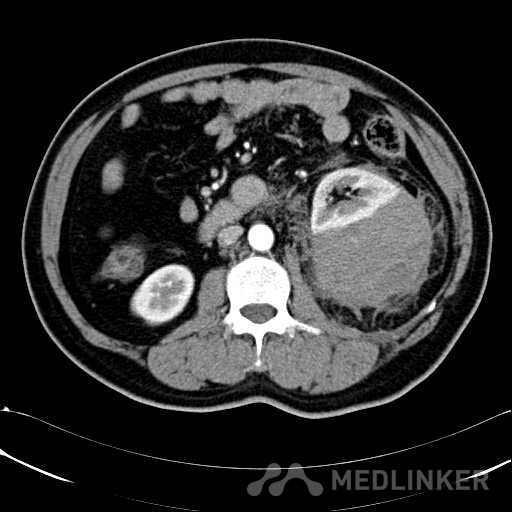

患者是54岁男性 主 诉: 突发左腰部疼痛3小时。 现病史: 缘于入院前3小时患者无明显诱因出现左腰部剧烈疼痛,无向他处放射,与活动及体位无明显关系,伴有腹胀、恶心、呕吐,无头痛、头晕,无人事不省、口吐白沫,无胸闷、胸痛、咯血,无发热、畏冷、寒战,大小便未解,肛门无停止排气,遂就诊我院,查“泌尿系彩超:左肾实质及不均质回声区,范围约9.4*4.1cm,界不清,内未见明显血流信号”,为进一步治疗,门诊拟“左肾占位”收住入院,发病以来,患者精神欠佳,未进食,大小便如前述,体重无明显改变。 患有“高血压病”7年,规则服药治疗(具体不详),监测血压情况不详。 T: 36.5 ℃ P: 65 次/分 R: 20 次/分 BP: 154/94 mmHg 双肾区皮肤无红肿、破溃及隆起,双肾肋下均不能被触及,左侧肾区叩击痛明显,右侧肾区无叩击痛,双侧肾区未闻及血管杂音。膀胱区无隆起,无压痛,耻骨上膀胱区叩诊空虚。外生殖器发育正常。 2016-04-12 泌尿系彩超:左肾实质及不均质回声区,范围约9.4*4.1cm,界不清,内未见明显血流信号。 04-12血常规:血红蛋白 151 g/L,白细胞 16.80 10^9/L,中性粒细胞百分比 84.90 %。急诊生化:白蛋白 39.8 g/L,葡萄糖 9.46 mmol/L。